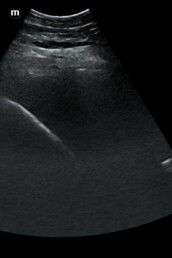

Weiterführende Untersuchungen

- Ultraschalluntersuchung der Leber aufgrund auffällig hoher Leberwerte im Blut

- möglicher Zusammenhang mit EMS/Übergewicht -> auch andere Ursachen bspw. Fettleber, Parasiten, Vergiftung denkbar

- Ultraschall lässt Verfettung der Leber vermuten